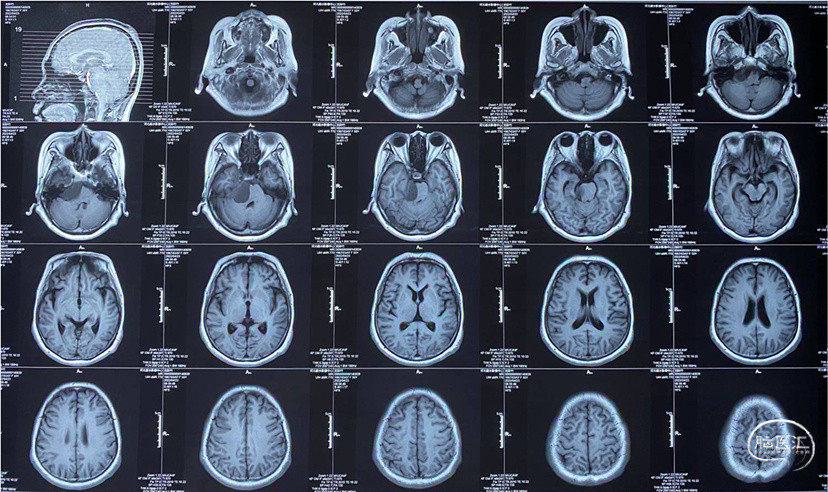

患者男性,51岁;

主诉:头晕2月,间断复视1月;

查体:神志清楚,右侧外下方复视;

辅助检查:头颅MRI增强影像诊断:右环池占位,神经鞘瘤可能,请结合临床及MRI平扫原片。